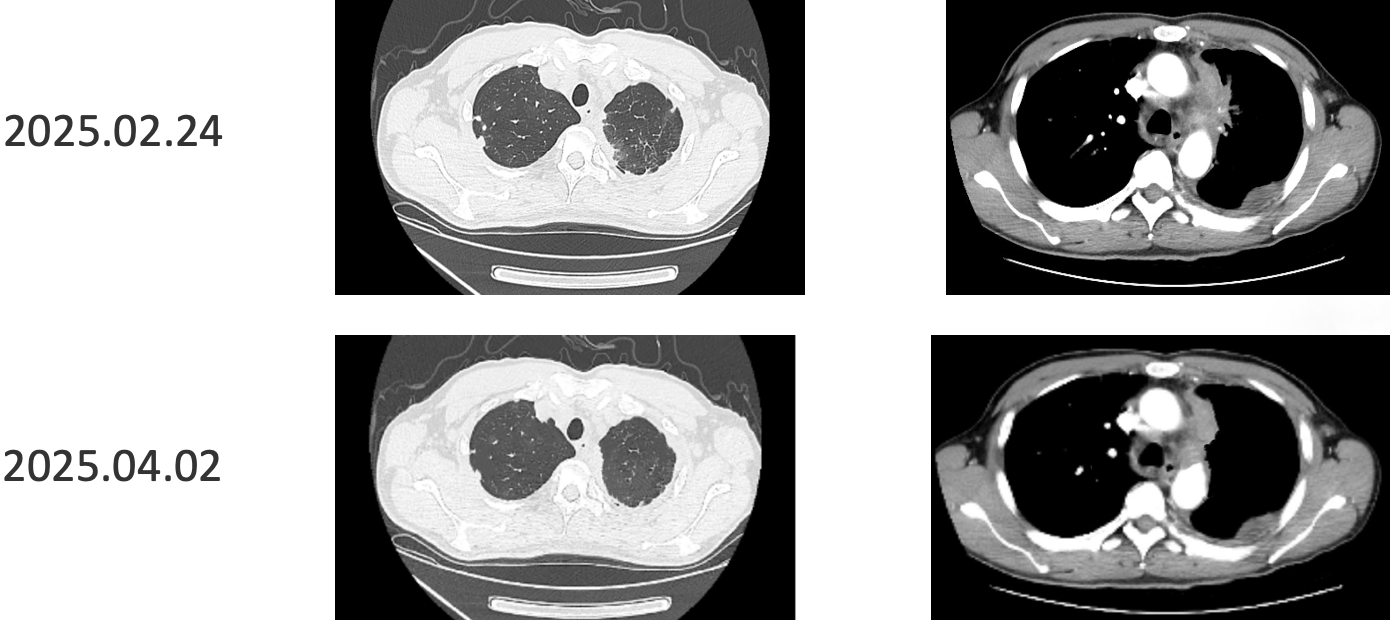

患者采用艾托组合抗体(PD-1/CTLA-4组合抗体)联合卡铂和安罗替尼治疗,同时进行血管内皮抑素胸腔灌注控制胸水。第一周期治疗后出现发热气喘等不良反应,经对症处理后症状改善。6周期治疗后影像学评估显示肺部病灶明显缩小,肝脏及淋巴结转移灶缩小,胸腔积液减少,疗效评价为PR(部分缓解),患者临床症状明显改善,生活质量显著提升。

1. 艾托组合抗体联合方案治疗6周期后,患者肺部病灶明显缩小,肝脏及淋巴结转移灶缩小,胸腔积液减少,疗效评价为PR(部分缓解);

治疗结果证实我们的选择是正确的。患者接受艾托组合抗体联合卡铂和安罗替尼治疗后,肿瘤病灶明显缩小,肝脏及淋巴结转移灶缩小,胸腔积液减少,临床获益显著,疗效评价为PR。

姚菲教授:在本例患者的治疗过程中,艾托组合抗体联合化疗和抗血管生成药物治疗对免疫治疗耐药及多线治疗后进展的NSCLC患者显示出良好疗效。患者迅速获得临床缓解,影像学评估显示病灶明显缩小,体现了艾托组合抗体克服PD-1抑制剂耐药的特性,该例患者免疫再治疗挑战成功。